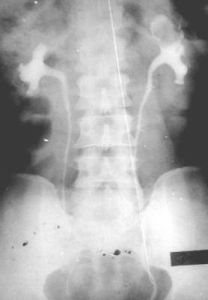

腎盂腫瘤2、逆行性泌尿系造影:其重要性為:

①造影更清晰,尤其是排泄性造影顯影不良時;

②可能見到病側輸尿管口噴血,下端輸尿管腫瘤向輸尿管口突出;

逆行造影時,腎盂內注入過多對比劑可能遮蓋小的充盈缺損,輸尿管造影必須使全輸尿管充盈方可明確診斷。球狀頭(bulb)導管輸尿管造影,其輸尿管導管頭似橄欖或橡子塊,插入輸尿管口螢屏

腎盂腫瘤輸尿管腫瘤時可使以下導管彎曲或呈圈狀。如插管通過腫瘤可發現其上方為清尿,而導管旁邊流出的為血尿。